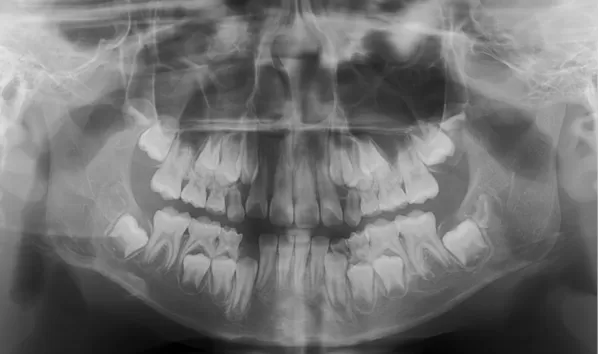

Rayons X avant le traitement

[Radiographie panoramique/Céphalogramme latéral]